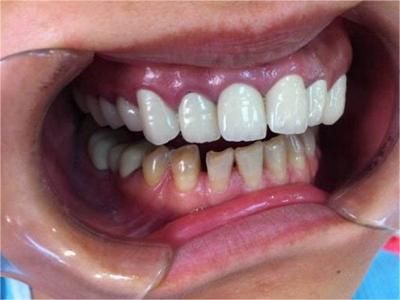

牙龈炎是发生于牙龈组织的炎症,患者可出现牙龈出血伴肿胀、发红、正常形态改变和偶尔不适等症状。本病主要由口腔卫生状况差导致,包括口腔不洁、牙菌斑等,诊断依据临床检查,治疗包括专业牙齿清洁和加强家庭口腔卫生。

牙龈炎患者可通过改善口腔卫生控制疾病,同时使用抗菌漱口液,如复方氯己定含漱液,并进行彻底的洁治处理。必要时,重新修整修复体的不良外形,并祛除局部刺激因素。